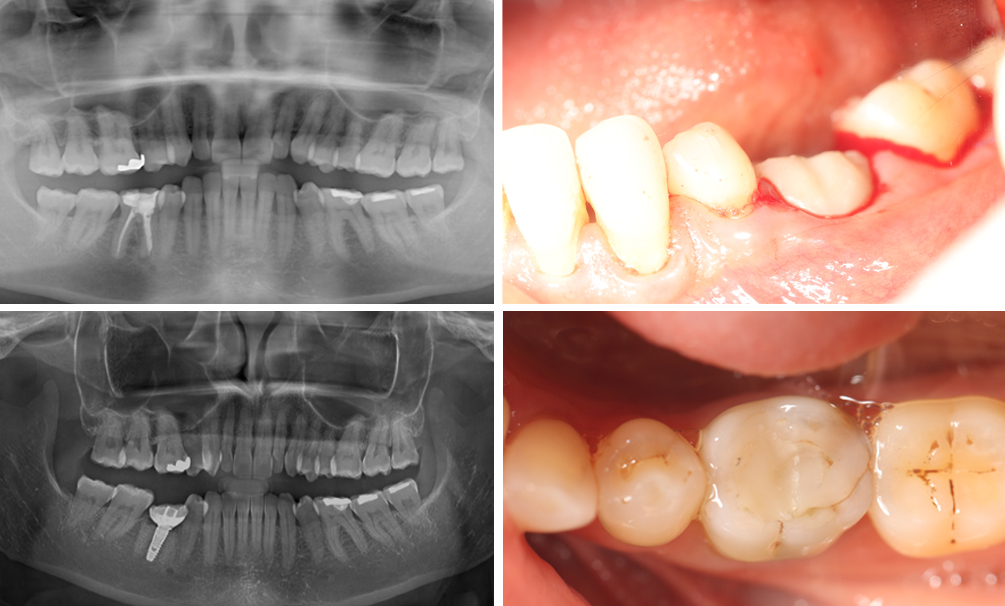

Implant

A természetes fog pótlására a legjobb megoldás az implantálás. A kemény szövetet és a lágyszövetet is mindig figyelembe kell venni, hogy egy tökéletes, hosszútávon működő eredményt tudjunk elérni.